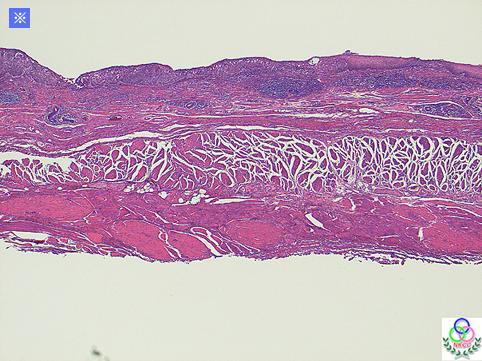

Criteria of Hist.ClassificationMalignant epithelial tumor/Squamous cell carcinoma

LocationEsophagus/Middle third

Technique, MethodHistology

Macroscopic TypesType 0/IIc (IIc) Superficial depressed type

Size40 -

Depth of Tumor Invasionmucosa